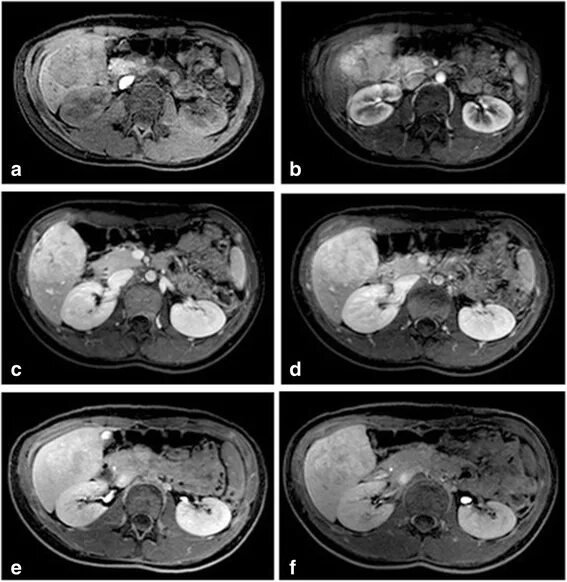

Подготовка к мрт печени